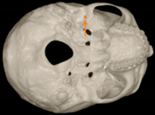

Three points determined the Acta plane: O, F right (FR), and F left (FL) (Table 2). Point O is the midpoint between the most craniodorsal point of the dorsum Sella and the most posterior dorsal point of the Basion in the midsagittal plane (Figure 1). Both points F are a result of the intersection between two lines: the line that connects the most inferior points of the lower orbital margins, right and left, and a line perpendicular to this line that runs through the most external points of the orbital margins, right and left (Figure 2). The new transverse reference plane, the Acta plane (Figure 2), is created by connecting the O-point (Figure 1) with FR and FL (Figure 2).

Figure 2.

(A) Construction of the F-points (right and left), frontal view. The F-points are originated from the intersection between the line connecting points A (the most inferior point of the lower orbit) and the perpendicular line to it that passes through points B (most external/lateral point of the Orbita). (B) Transverse view of the ACTA plane.

Different from the majority of the existing planes, the Acta plane was idealized for 3D use. Therefore, our goal was to determine both external and internal references in the skull. External references were determined from the orbital rim. The first reference line originated from the connection between the most inferior points of the left and right lower orbital margins. In order to keep the head facing forward, a line was traced perpendicularly to the first line, running through most of the external points of the left and right orbital margins. The intersection of these two lines resulted in point F, which orients the CBCT scan in the X-axis and Y-axis.